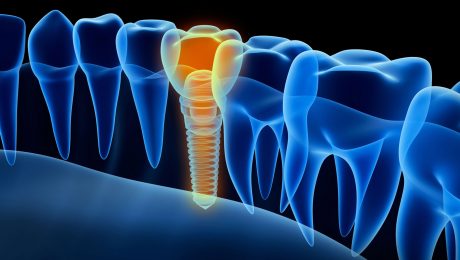

ایمپلنت دندان چیست؟

ایمپلنت دندان چیست؟ در واقع ایمپلنت دندان جایگزینی برای ریشه ی دندان از دست رفته می شود و همواره نیز از جنس فلز تیتانیوم تهیه و تولید می شود تا بتواند با بدن سازگار بوده و ایجاد مشکل نکند. در ادامه طریقه ی کاشت ایمپلنت و ویژگی های یک ایمپلنت خوب همچنین مزایا و معایب

در این مقاله میخواهیم پیرامون ایمپلنت دندان علی الخصوص مدت زمان ایمپلنت دندان در جراحی ایمپلنت مطالبی را به شما ارائه دهیم با ما همراه باشید. تعریف ایمپلنت ایمپلنت روشی است ، برای درمان دندان های از دست رفته و خالی ، که هم بر سلامت شخص و هم بر ظاهر شخص تاثیر گذار هستند

همه چیز در مورد کاشت دندان (ایمپلنت دندان)

گاهی بر اثر کهولت سن ، تصادفات شدید ، اتفاقات خطرناک ، پوسیدگی ریشه دندان ها و در نهایت لق شدن دندان ها باعث میشود دندان های فرد از دست برود. نبود دندان علاوه بر اختلال در زیبایی ، در غذا خوردن و تکلم نیز مشکلات شدیدی به وجود می آورد که تنها راه و

مراحل ایمپلنت دندان

مراحل ایمپلنت دندان مراحل ایمپلنت دندان به این صورت است که در ابتدا دندانپزشک با برسی کردن وضعیت فک از استحکام استخوان ها مطمئن میشود. استخوان ها اگر قدرت نداشته باشد قبل از انجام ایمپلنت باید استخوان ها را متوقف کرد و پیوند استخوان صورت گیرد و بعد از انجام پیوند استخوان 4 الی8ماه زمان